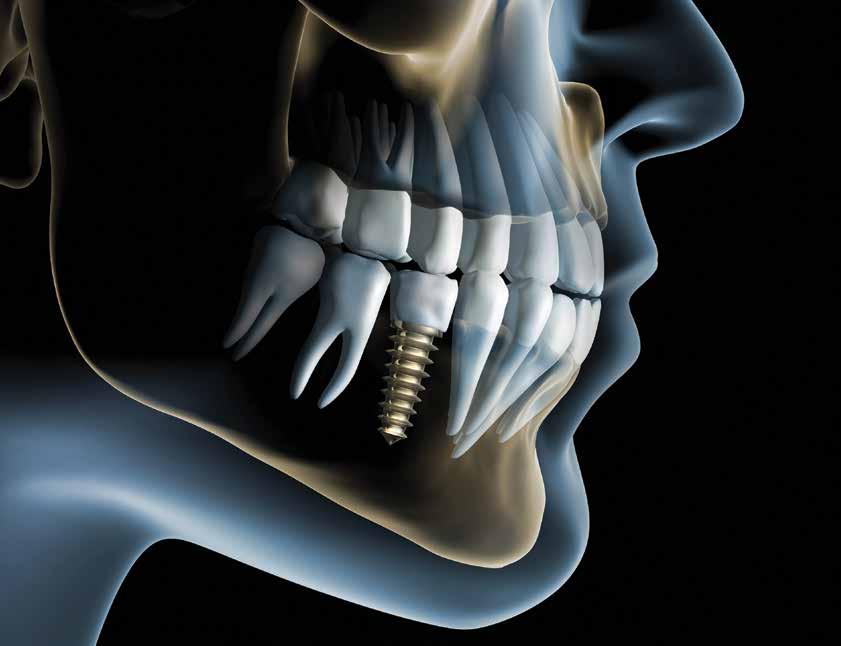

Did you know that the history of dental implants can be traced back to ancient Egypt where they carved seashells and stones to replace missing teeth? As early as 2000 B.C. early versions of dental implants were used in ancient China and the first recorded case of a replacement tooth made of metal came from the body of an Egyptian King around 1000 B.C. That was a long time ago. One of the most important developments that lead to our current dental implants occurred in 1957 when a Swedish orthopedic surgeon named Dr. Per-Ingvar Brånemark began studying bone healing and regeneration and discovered that bone could actually grow in proximity with titanium and could effectively adhere to the titanium and not be rejected. Brånemark called this “osteointegration.”

Now implants are commonplace and they come in many shapes, sizes and different coatings to enable the best integration into bone. In the general population, the use of dental implants has become a great treatment option for replacing missing teeth. It doesn’t matter the age, people want to replace missing teeth and they want to look younger, better and enjoy eating all foods again. Of course, dental implants are not inexpensive and patients can be concerned about finances and length of treatment time. Older adults have complex medical, social and economic issues that must be taken into consideration, and dentists need to give careful attention to help each patient consider the best tooth replacement therapy.

New advances in digital dentistry have enabled more advanced diagnostic information. The dentist can now use a surgical guide or denture to indicate the desired implant position, angulation and need for hard and/or soft tissue augmentation before or during implant placement. Guided implant surgery with the use of cone-beam computed tomography scans and intraoral scanners have made it possible to get the best position and restoration for the patient.